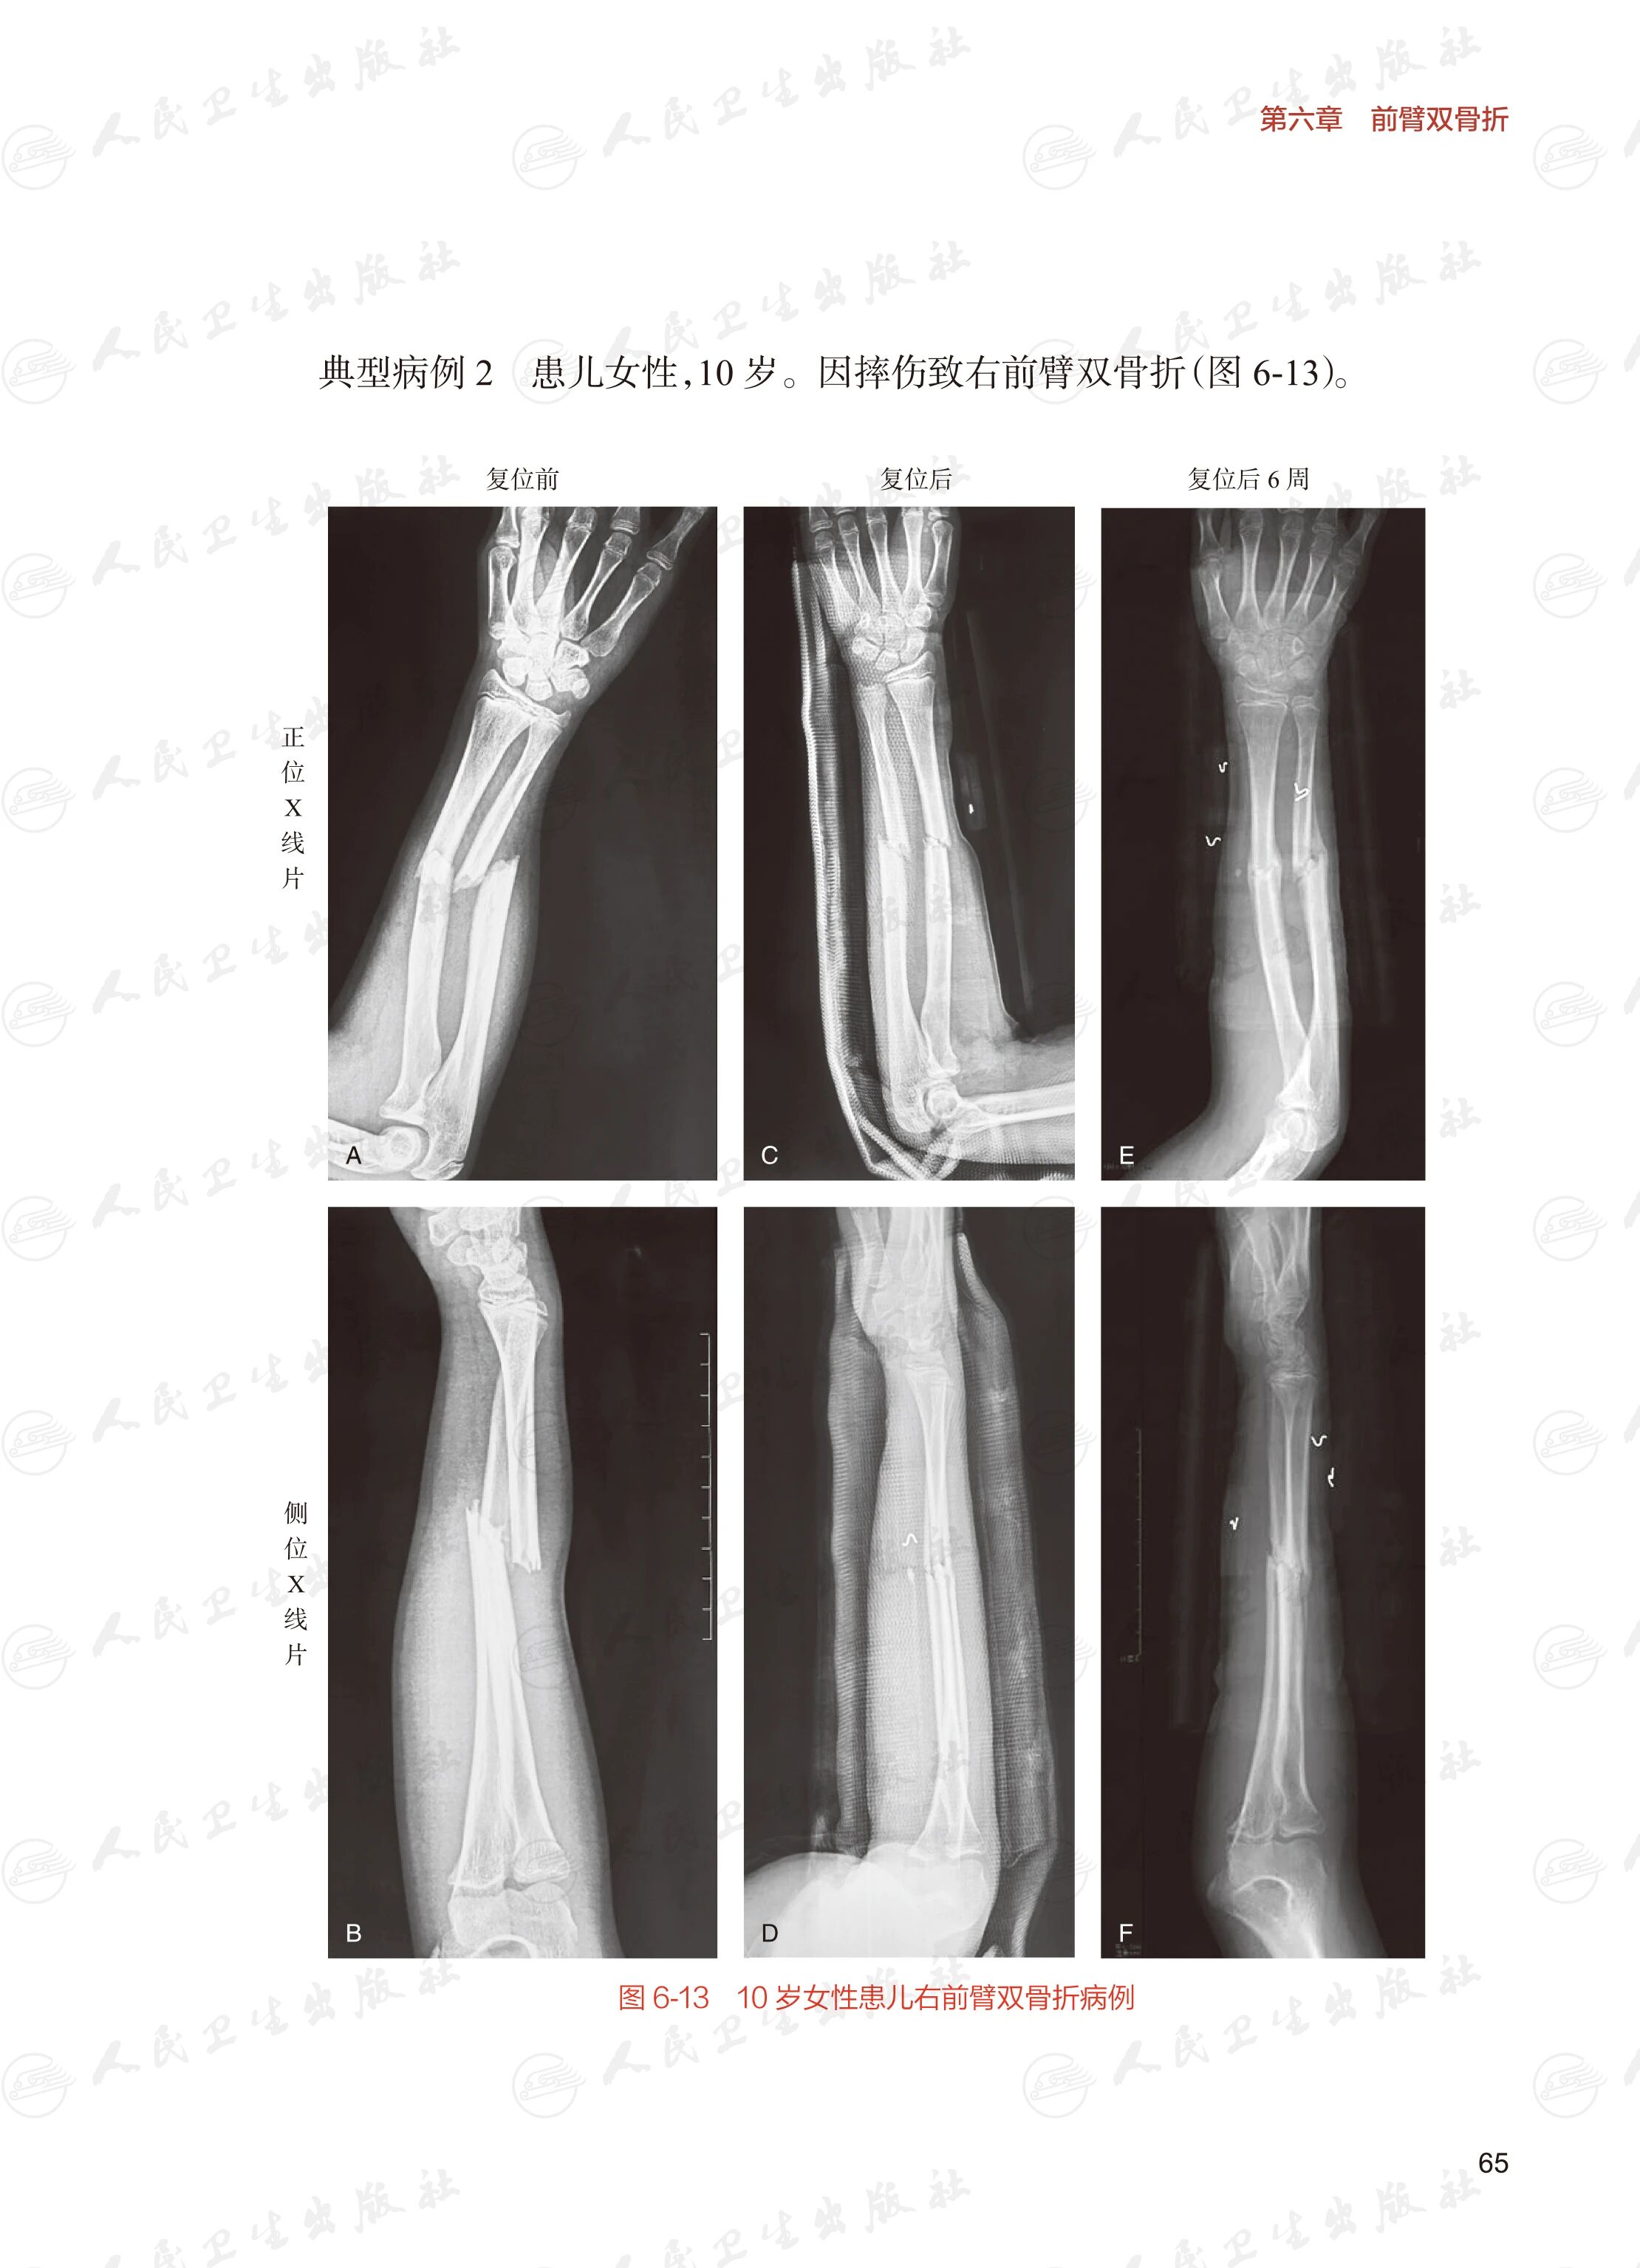

对于临床常见的四肢非开放性骨折而言,使用闭合复位技术治疗,具有省时、省力、并发症少、骨折愈合快等优点。在介绍各部位骨折所使用的闭合复位技术内容中,通过详细图解、视频演示的方式使读者看了就能懂,懂了就能用。对全身各部位关节脱位的手法复位操作要点进行详细介绍。本版较上一版增加了对儿童常见骨折治疗的新技术的介绍。此外,本书还介绍了对于成人或儿童干骺端骨折使用经皮穿针固定替代传统的石膏或夹板固定的经验。

骨科临床实践中的骨折治疗金标准有三大核心原则:疗效确切、并发症可控、医疗成本优化。虽然目前骨折的主要治疗方法仍然为手术治疗,但并不是所有的骨折都需要手术治疗。本书系统阐述了四肢骨折闭合手法复位的适应证及关键技术要点,通过详细图解与病例影像相结合的方式,帮助读者快速掌握技术精髓并应用于临床实践。